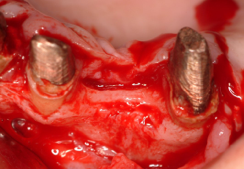

インプラントは歯茎の中の骨がないと植立できません。そのため、その骨が足りない場合が一番、インプラントをする上で問題となります。下顎では過下顎神経管という太い神経が顎の骨の中に通っていますので歯茎からその神経が近い場合骨移植が必要となります。また、上顎では太い神経はありませんが、副鼻腔という大きな空洞が顎の中にありますので、歯茎から副鼻腔が近い場合も骨移植が必要となります。

骨移植はインプラント埋入より、高度な技術が必要ですのでなるべくこの処置をしなくて済むように考案されたのがオールオン4などのコンセプトです。しかし、オールオン4ができないくらい骨がたりない場合などには行います。